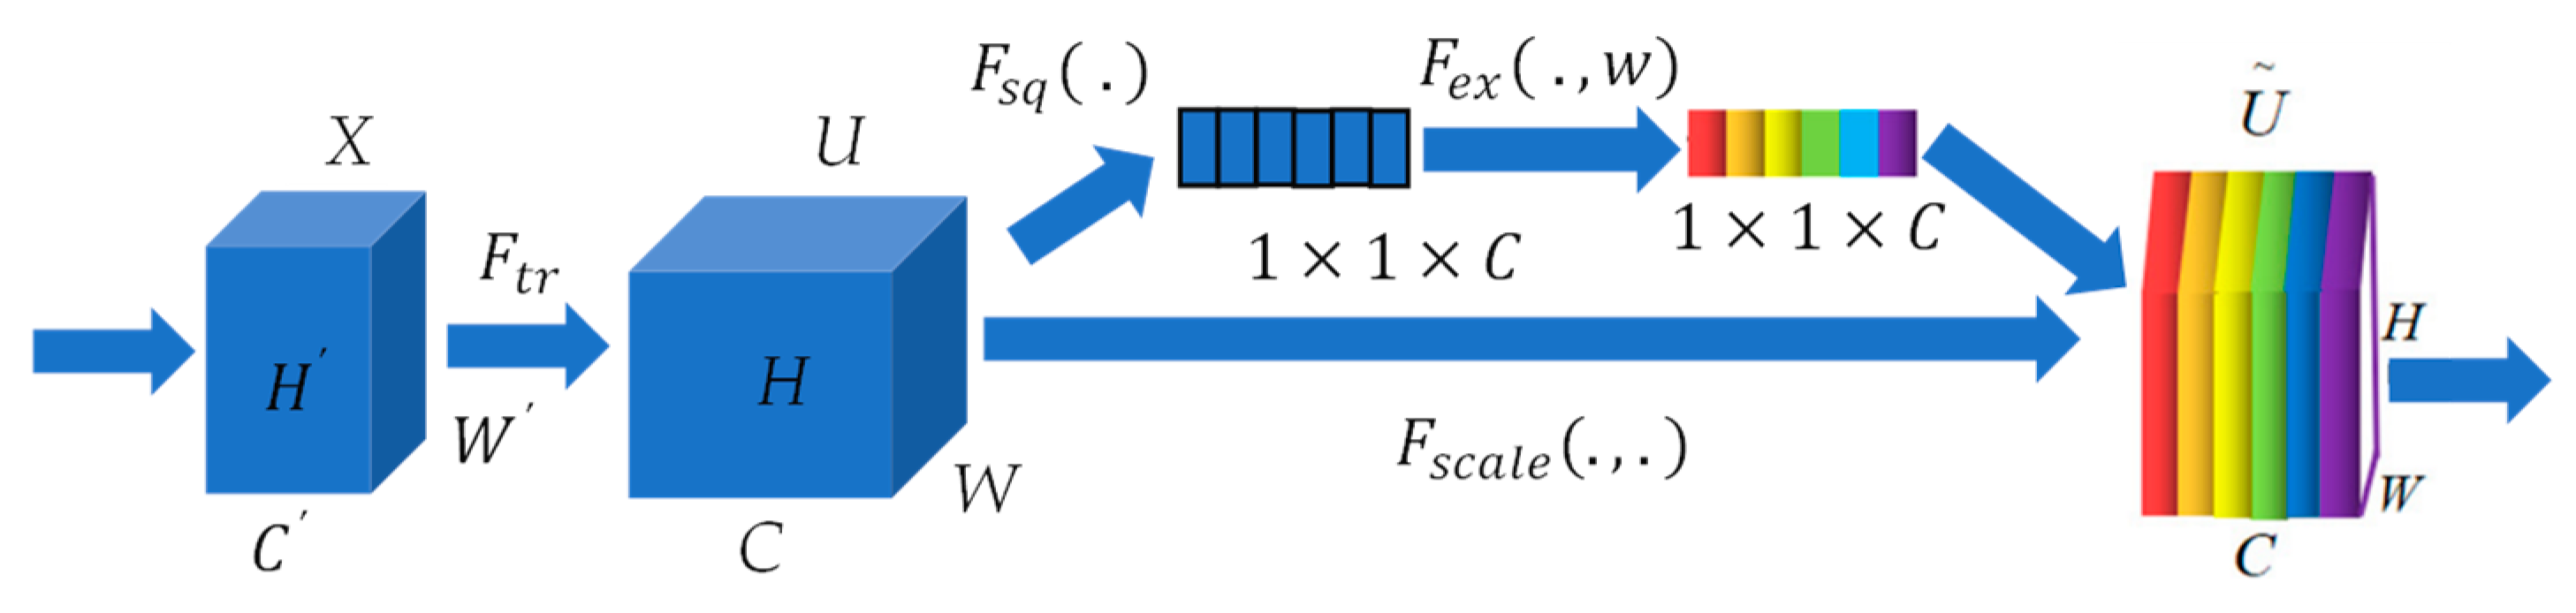

3.3. SE Block

The attention mechanism functions as a mechanism for resource allocation and can be categorized into various types, including channel attention, pixel attention, multistage attention, and others. In this study, we focus on the channel attention SE block, as introduced in [

32]. The fundamental concept of this block is to determine feature weights based on the loss, assigning greater weight to effective feature maps. The SE block consists primarily of two components: squeeze and excitation.

The squeeze operation in neural network architectures compresses features along the spatial dimensions, effectively transforming each two-dimensional feature map into a single real number. This compression process generates a global receptive field, allowing the network to capture and respond to global information present in the input data. On the other hand, the excitation step is akin to the gating mechanism found in Recurrent Neural Networks (RNNs). This mechanism involves selectively amplifying or dampening specific features based on their relevance to the task at hand, enabling the network to focus on the most informative parts of the input data. Together, squeeze and excitation operations allow a neural network to dynamically adjust the importance of different channels, enhancing its ability to learn complex patterns and relationships in the data. It generates weights for each feature channel using parameters and learns these weights to explicitly model the correlation between feature channels. The graphical representation of the SE block is depicted in

Figure 4. For any given transformation

, mapping the input

to the feature map

where

, we can construct a corresponding SE block to perform feature recalibration. The feature

first passes through a squeeze operation

, which compresses

into a

feature. Next, through excitation operation

, the feature from

is excited. Lastly, through

, the recalibration feature is achieved, where

implies that the weights assigned to the excitation output are individually applied to each preceding feature channel through multiplication. Through this process, the original characteristics in the channel dimension are recalibrated, achieving a fine-tuning of the importance of each feature channel.